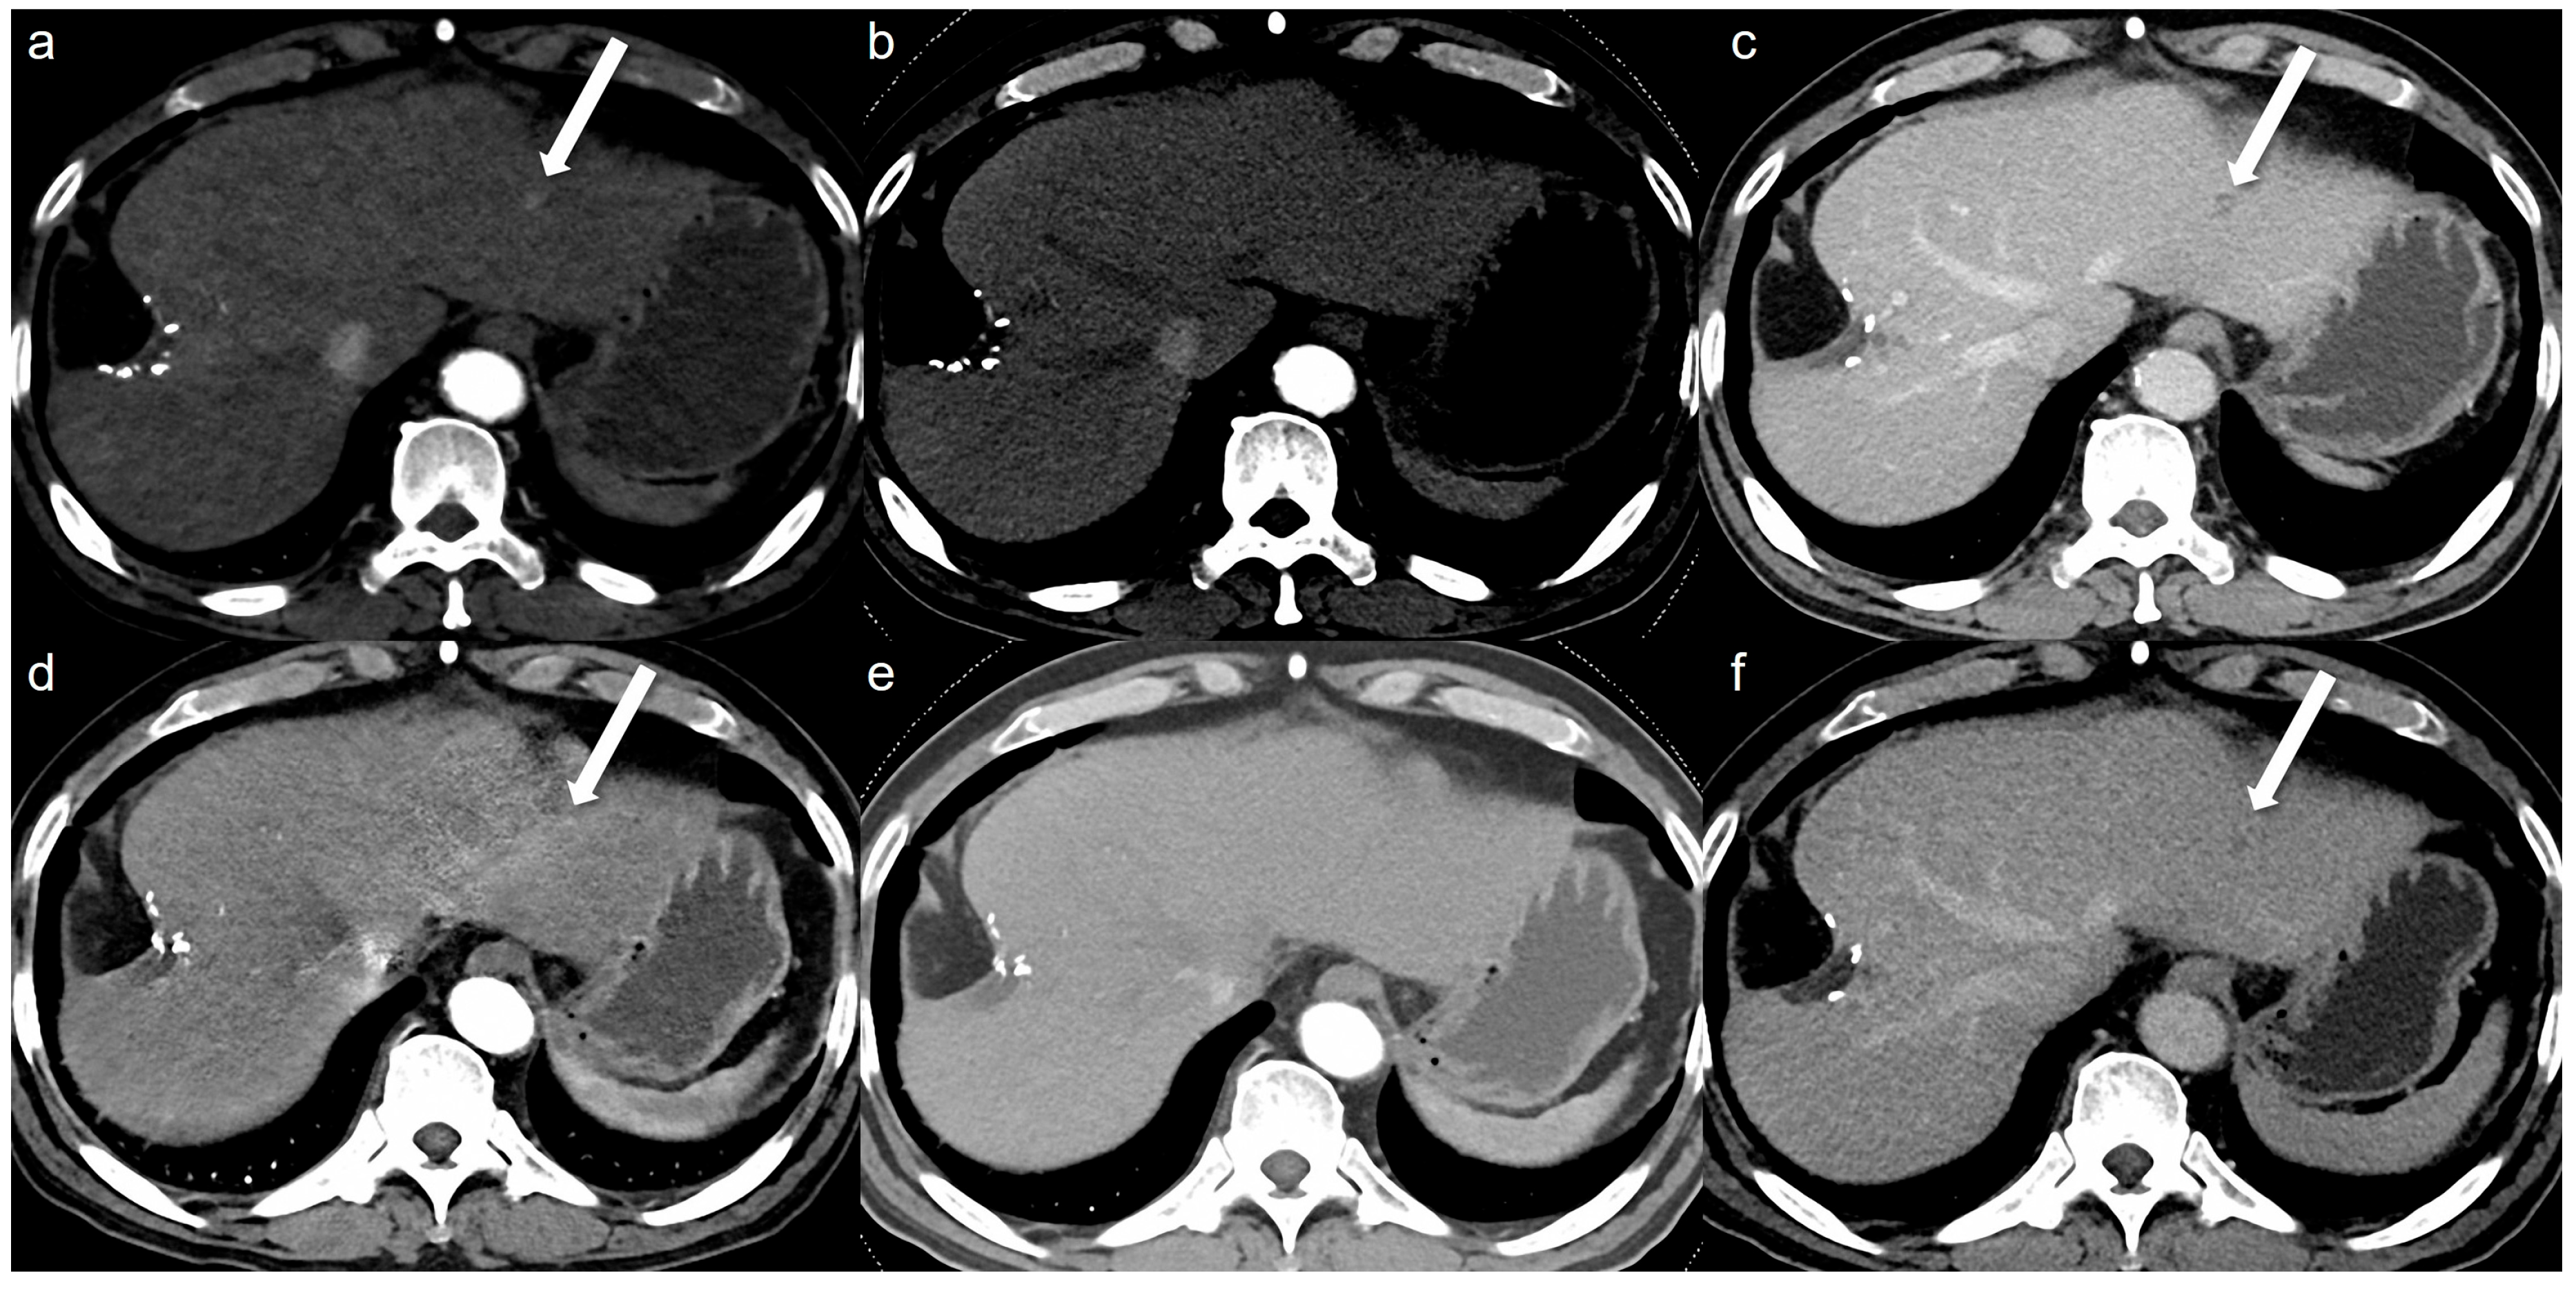

- Bae, J.S.; Lee, J.M.; Kim, S.W.; Park, S.; Han, S.; Yoon, J.H.; Joo, I.; Hong, H. Low-contrast-dose liver CT using low monoenergetic images with deep learning–based denoising for assessing hepatocellular carcinoma: A randomized controlled noninferiority trial. Eur. Radiol. 2023, 33, 4344–4354. [Google Scholar] [CrossRef]